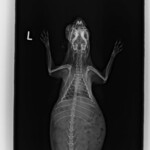

Pirátka Amálka již odcestovala do nového domova. Domov našla v Olomouci a i nadále bude pravidelně navštěvovat MVDr Agátu Sívkovou, která se o ní celou dobu skvěle starala. Amálce se pomoci dostalo opravdu na poslední chvíli. Její majitelé absolutně zanedbali péči o ní a pomoci se jí dostalo opravdu za 5 minut 12. První operaci podstoupila v psím azylu Zastavme utrpení z.s. a nadále jsme Amálku přijali pod svá ochranná křídla my. Díky vážnosti jejího stavu byla Amálka po celou dobu léčby v dočasné péči veterinářky, která dohlížela na její zdravotní stav. Podstoupila CT vyšetření a několik složitých operací (včetně sekání jařmové kosti) a i přesto, že její šance na přežití byly 50 na 50 jsme velice rádi, že jsme to nevzdali. Amálka je již v rámci možností v pořádku. Její zdravotní handicap ani komplikovanější povaha neodradila vážnou zájemkyni a králičce se tak naskytla skvělá příležitost nového domova v Olomouci kde jí budou dělat společnost dva králičí kamarádi Fousek a Albert. My bychom tímto chtěli poděkovat MVDr Sívkové za skvělou péči, MVDr Jeklovi a Hauptmanovi za provedení CT vyšetření a operací a samozřejmě i vám – našim fanouškům, kteří nás podporují a bez kterých bychom nikdy nemohli pomáhat v takové míře v jaké pomáháme a králíčkům bychom tak nemohli poskytnout nadstandardní veterinární péči. Děkujeme, že jste v tom s námi!